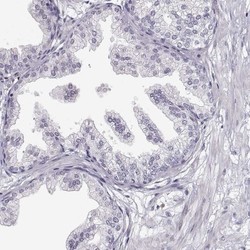

- Immunohistochemistry-Paraffin: VGF Antibody [NBP2-31596] - Staining of human prostate shows no positivity in glandular cells as expected.